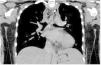

This is the case of a 17-year-old girl with a past medical history of childhood meningoencephalitis without sequelae, with a 1-week history of neck pain, odynophagia, and fever of up to 39 °C. On physical examination, vital signs were stable, and she exhibited cervical pain upon movement. The lab test results showed elevated acute-phase reactants. The cervical and thoracic CT scans performed revealed the presence of a large cervical collection with abundant gas bubbles inside (asterisks) spreading toward the posterior mediastinum through the retropharyngeal space, which were findings consistent with necrotizing fasciitis and posterior mediastinitis. Surgical samples cultured Streptococcus dysgalactiae and S. intermedius. The patient responded favorably to antibiotic therapy and surgical drainage of the collection (Figs. 1, 2 and 3).